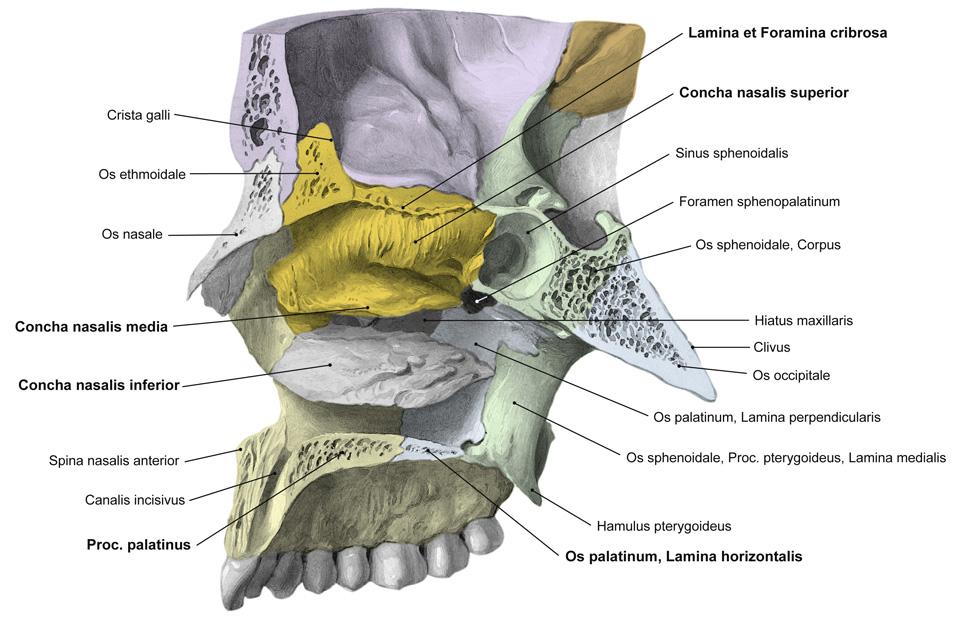

Fig 3.10a: a. maxillaris - sfenomaxillair deel

|

|

Fig 3.10b: a. maxillaris - sfenomaxillair deel - neusholte

|

|